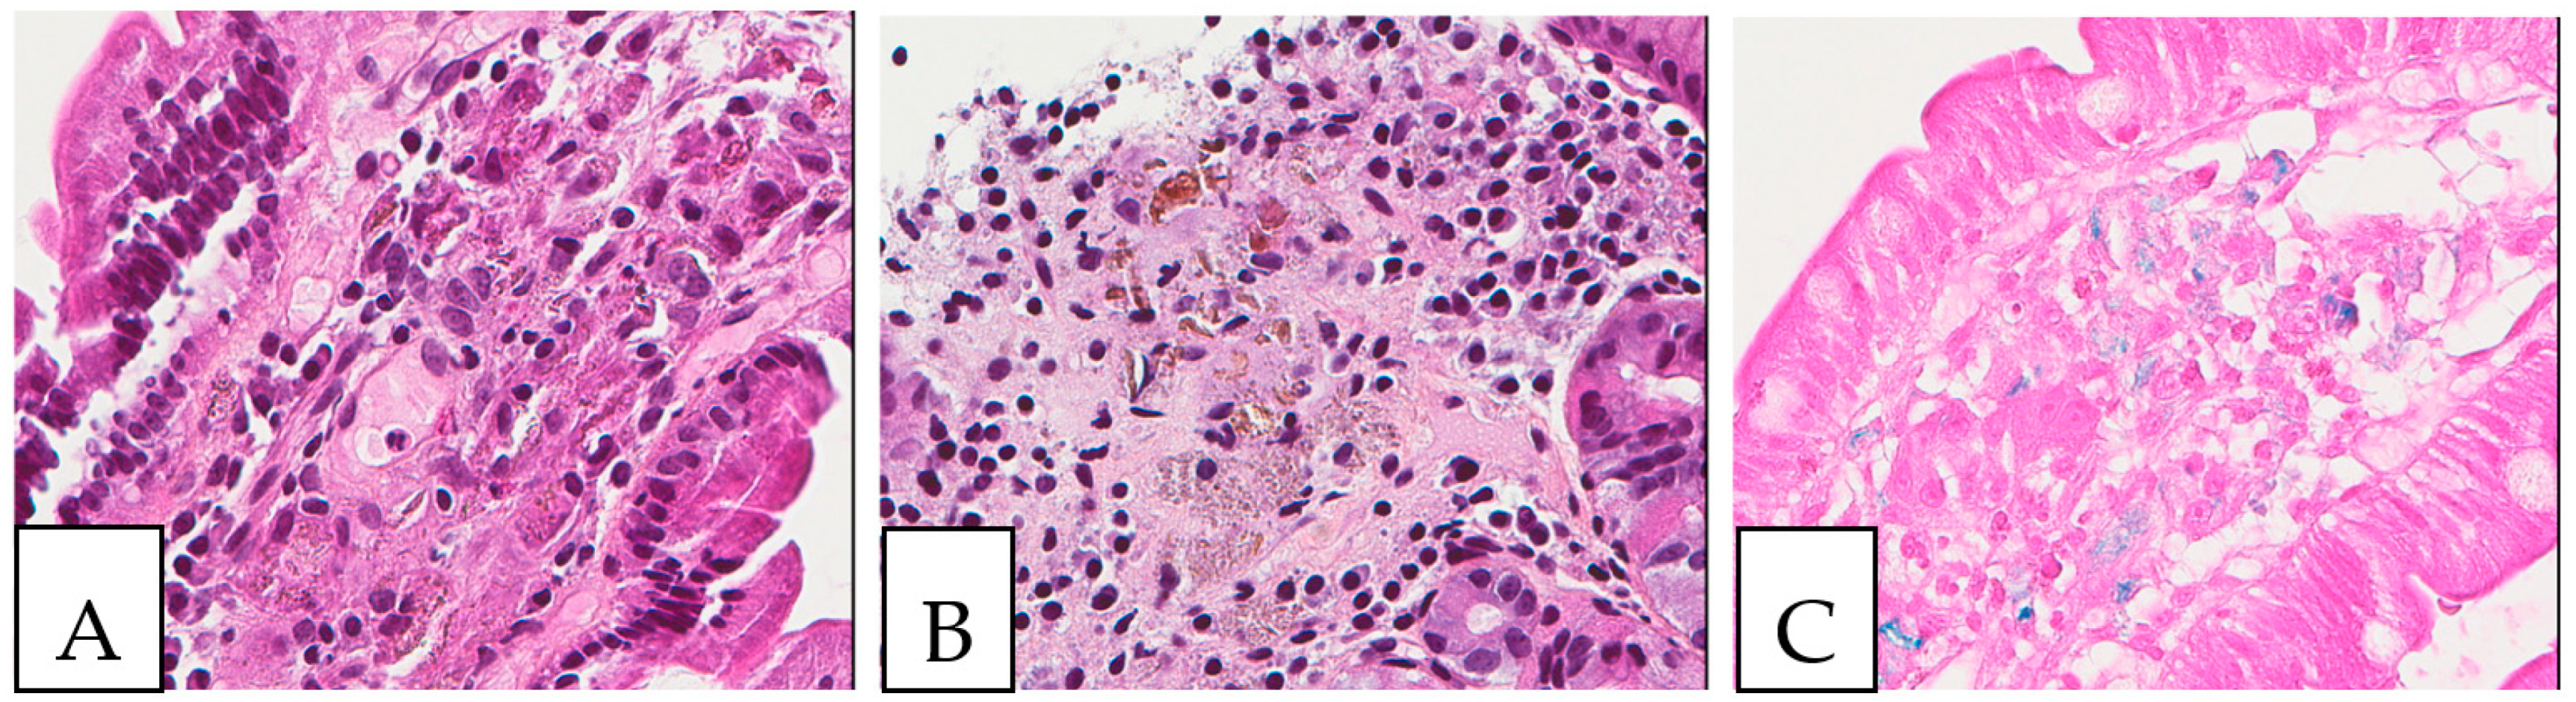

Figure 1.

(A,B) Crystal-storing histiocytosis is characterized by an accumulation of histiocytes with intracytoplasmic crystalline inclusions (arrows). (A,B) High magnification of samples from two different cases. (A) A 70-year-old male who presented with abdominal pain, cervical lymphadenopathy, and weight loss with colonic white mucosal elevations on endoscopy. (B) A 50-year-old male with a suspicious lesion of the cavum.

Crystal storing histiocytosis. (A) Morphology of samples affected by crystal-storing histiocytosis, (B) CD68-positive histiocytes, (C) S100-negative lesion. This specimen is from the same patient described in Figure 1 (A) and was taken from a colonic white mucosal elevation.